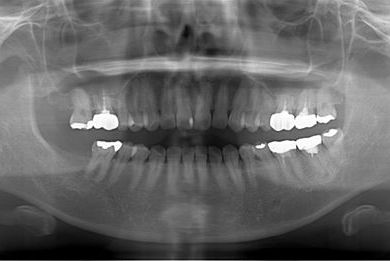

| 性別/年齢 | 女性 / 39歳 | ||||||||||||||||||||||||||||||||

| 主訴 | 右奥歯の虫歯と、右奥のインプラント治療について相談。 | ||||||||||||||||||||||||||||||||

| 治療方針 | 右下奥欠損部分をインプラント治療にて、機能的・審美的回復を行う。 | ||||||||||||||||||||||||||||||||

| 治療内容 | インプラント1本、ハイブリッドセラミッククラウン1本 | ||||||||||||||||||||||||||||||||

| 総治療費 | 329,963円 | ||||||||||||||||||||||||||||||||

| 治療期間 | 5ヶ月 |